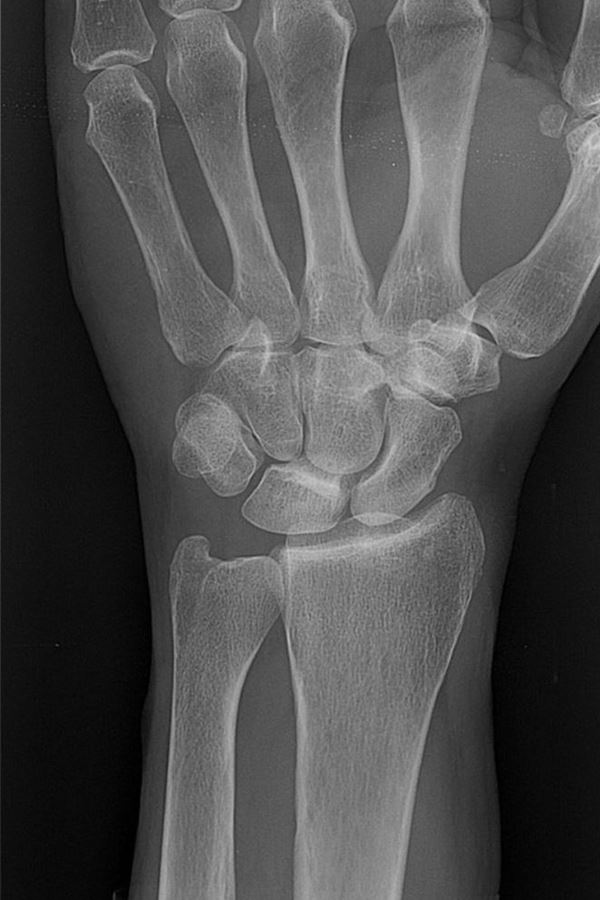

Normale linker pols

De meest voorkomende fractuur is de distale fractuur van de radius. Het is belangrijk dat de arts weet welk type fractuur u hebt. Het type bepaalt namelijk de behandeling.